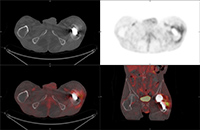

63 year-old woman with right femoral hardware for 3 years presented with right leg pain. Whole body Tc-99m HMPAO tagged WBC (A) scan demonstrated focal abnormal activity in the distal right femur which may represent infection or focal marrow. Tc99m sulphur colloid bone marrow scan (B) four weeks later demonstrates similar focal uptake in the distal right femur confirming the etiology as uptake in displaced marrow and not infection. 60 year-old man with history of lung cancer and left hip arthroplasty suffered from stiffness in the left hip region. Axial CT, FDG PET, fused axial, and coronal PET-CT demonstrates increased uptake of FDG in heterotopic ossification in the musculature of the left thigh. 30 year-old woman with history of lymphoma. Axial CT, PET, PET-CT fused, and PET MIP images demonstrate intense FDG activity in the bilateral neck and paravertebral regions with a symmetrical distribution. Cross-sectional images clearly show that activity in the neck corresponds to fat and therefore consistent with brown fat activity. Brown fat activity is seen more commonly in younger patients and is also increased in response to hypothermia (so keep patients warm both pre and post injection of FDG).

Figure 35A Figure 35B

PA Chest radiograph (A) demonstrates a sternal cage. Whole body Tc99m MDP images (B) demonstrate focal radiotracer activity in ribs bilaterally on the anterior view representing the sites of sternal cage fixation with bony reaction.